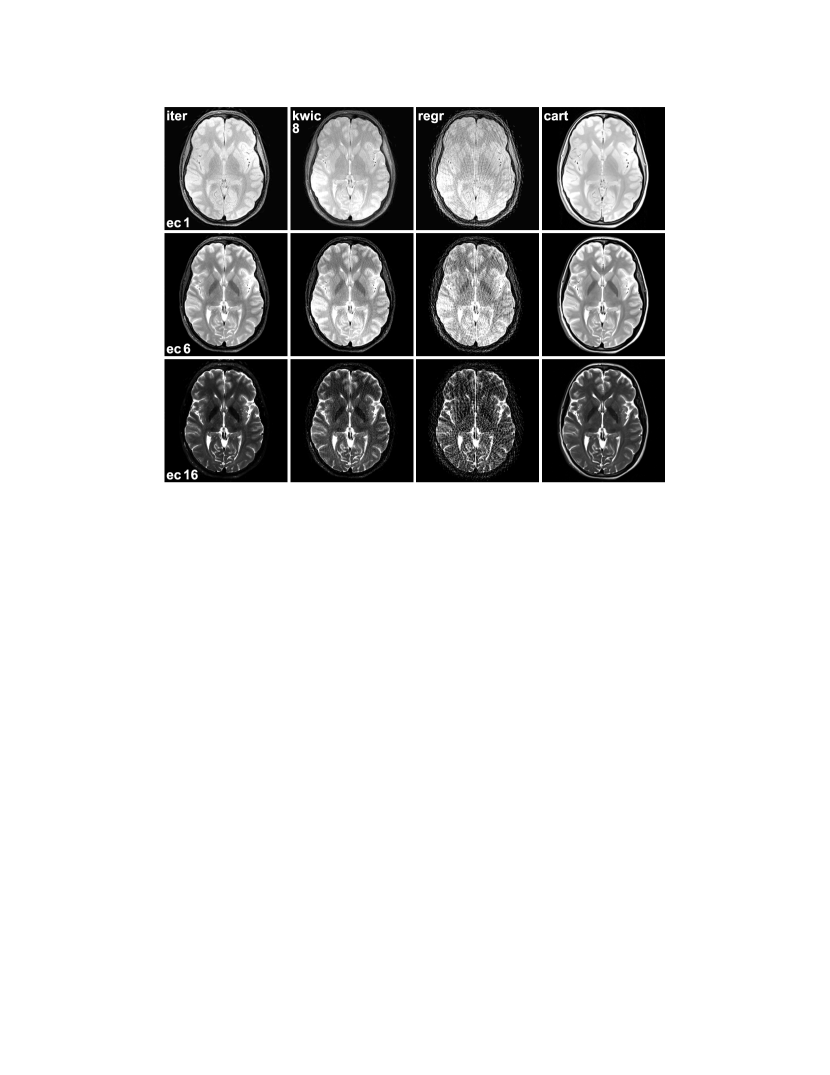

For the same radial data set, Fig. 3 compares snapshots of the first, 6th, and last echo reconstructed using the proposed method with Eq. (14), direct gridding, and KWIC with sharing of 8 echoes. Corresponding images from the Cartesian data set are shown as reference. The contrast of the Cartesian and gridding images can be taken as ground truth due to the equal echo time of all k-space data used. It can be seen that the snapshots calculated with the proposed method show good match to the contrast of the Cartesian gold standard while they are not affected by streaking artifacts.